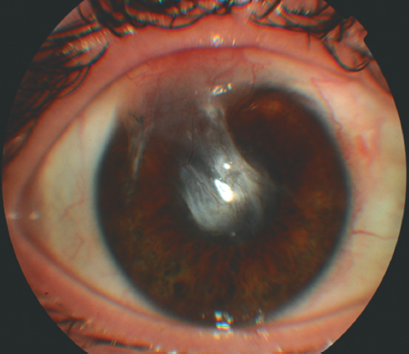

Biomicroscopy of the left eye revealed edema and hyperemia of the eyelids, as well as pronounced mixed injection of the eyeball, conjunctival chemosis, and in the optical and paraoptic zones of the cornea there was a white ring-shaped infiltrate with fuzzy contours and fusion in the center, d = 6.0 mm. The edges of the infiltrate reached the limbus in the vertical meridian. Reduced corneal sensitivity was found. The AC was shallower than in average. Opalescence of aqueous humor was “+++”, and 3 mm hypopyon was present. The pupil was round and in the center, d = 4.0 mm; there was no pupil reaction to light. Detailed ophthalmoscopy was difficult owing to the state of the cornea. A plain B-scan revealed no ultrasound pathology (Fig. 8).

Fig. 8. Patient K. Photo of the eye on admission

Рис. 8. Пациент К. Фото глаза при поступлении

In order to verify the diagnosis, a corneal confocal microscopy was performed with an HRT 3 device with a corneal module (Heidelberg Retina Tomograph Rostock Cornea Module). In the middle stroma of the stria there was an edema of the ground substances. Bright fusiform structures – pseudofilaments of Candida – and hyperreflective bilayer structures – Acanthamoeba cysts – were visualized in the layers of the middle stroma. The deeper layers of the cornea could not be visualized. The histopathology of the keratitis was of mixed (bacterial, Acanthamoeba, and fungal) etiology (Fig. 9). A washing from the cornea for Acanthamoebae was performed. Microscopy of the sediment revealed Acanthamoebae and bacteria; inoculation from the cornea and conjunctiva for the culture and sensitivity to antibiotics, on Sabouraud’s medium, was negative.